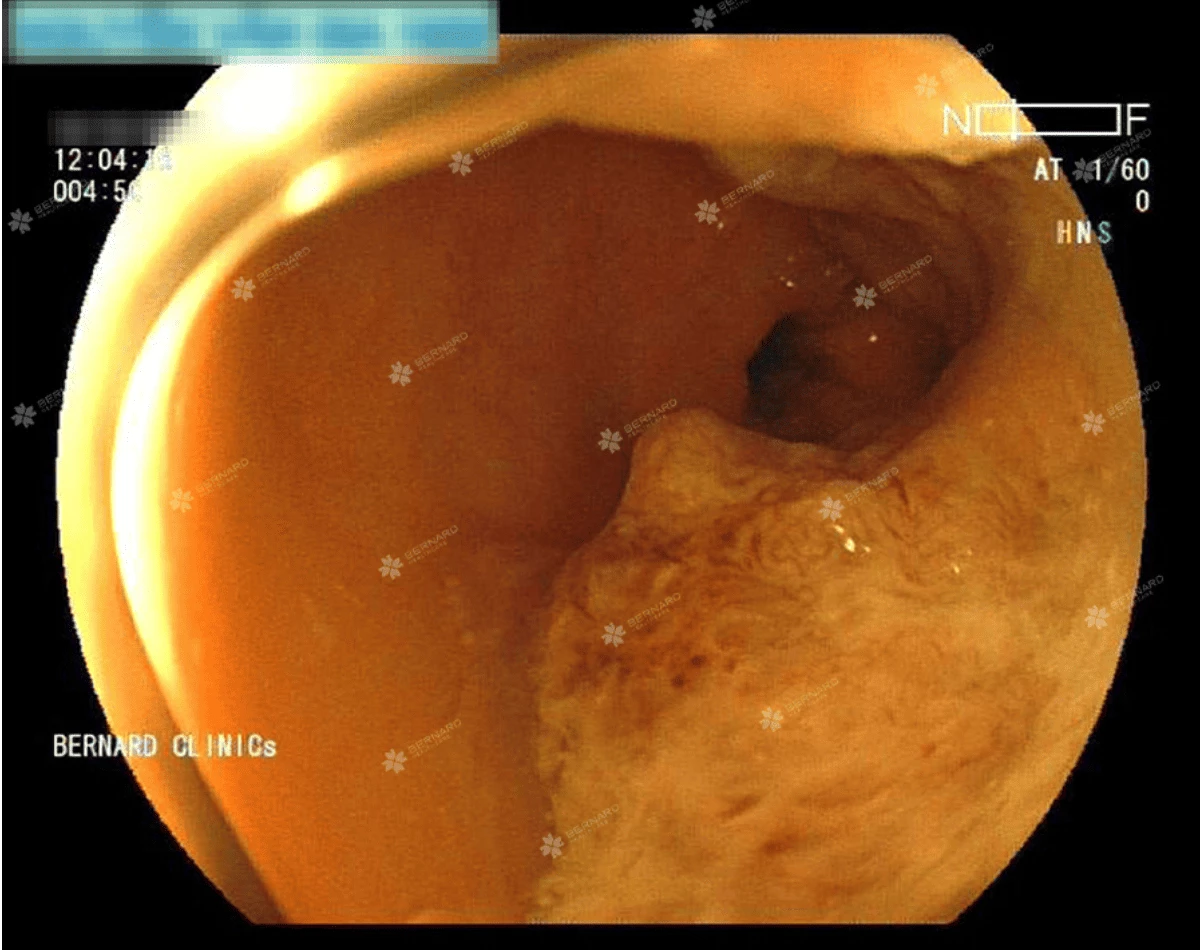

Nội soi toàn bộ đại trực tràng phát hiện ung thư tái phát và ung thư mới

Tại trực tràng, cách hậu môn khoảng 10cm, vị trí miệng nối sau phẫu thuật vẫn còn chỉ khâu xuất hiện khối u sùi, nhiễm cứng, làm hẹp lòng ruột, nghi ngờ tái phát ung thư trực tràng. Đáng lo ngại hơn khi soi về phía manh tràng, bác sĩ nội soi tìm thấy cách hậu môn nhân tạo #8cm có tổn thương u sùi, gây hẹp lòng.